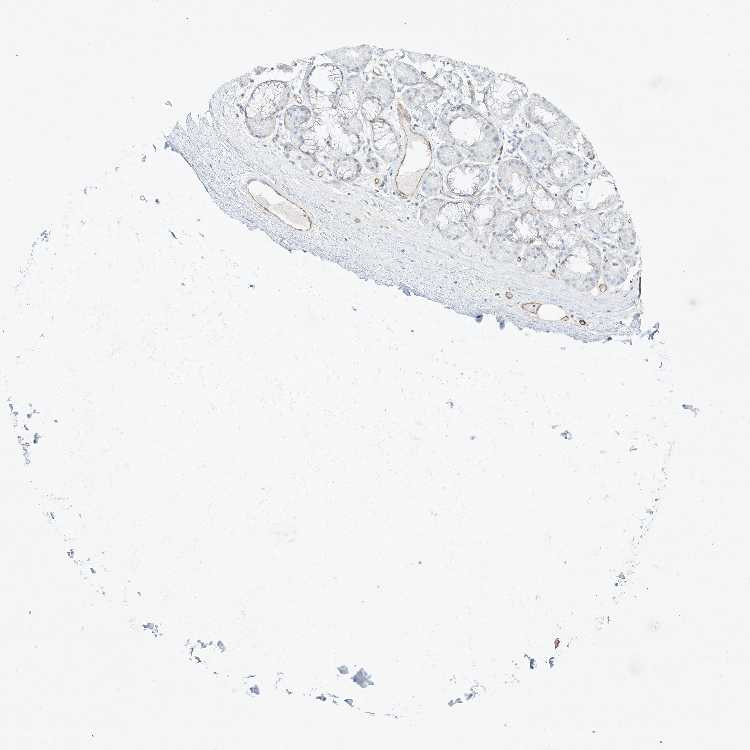

TISSUE PRIMARY DATA SOFT TISSUE Show tissue menu

SOFT TISSUE 1 - Antibody stainingi

Antibody staining in the annotated cell types in the current human tissue is reported as not detected, low, medium, or high, based on conventional immunohistochemistry profiling in selected tissues. This score is based on the combination of the staining intensity and fraction of stained cells.

Each image is clickable and will lead to virtual microscopy that enables deeper exploration of all samples and also displays staining intensity scores, fraction scores and subcellular localization as well as patient and tissue information for each sample.

Antibody HPA031813Antibody HPA076571

Chondrocytes -Not detected

Fibroblasts LowNot detected

Peripheral nerve Not detected-